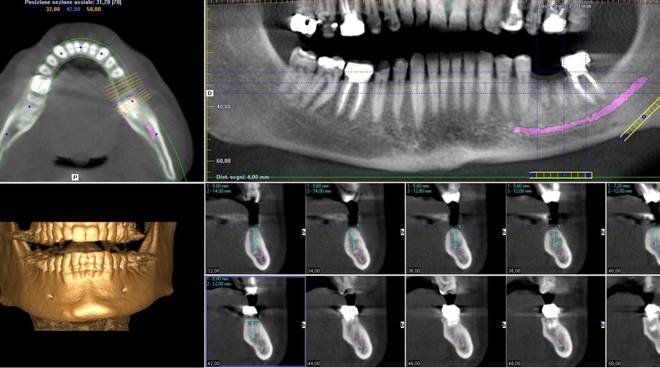

Ulteriore metodica di ultima generazione, la Cone Beam 3D, disponibile presso il Centro di Sciacca e di Ribera, si avvale di raggi X per acquisire una porzione del massiccio facciale, in particolare le arcate dentarie. La Cone Beam 3D viene utilizzata prevalentemente nella valutazione pre-operatoria in implantologia dentale.

Il macchinario di recente installazione che utilizziamo al Centro Radiologia Tagliavia, la Cone Beam Orthophos SL, permette l’acquisizione del volume desiderato in pochi secondi e attraverso le tecniche di post-processing e le ricostruzioni 3D, consente una migliore pianificazione pre-operatoria (misurazioni, densità) e una immediata visualizzazione delle arcate dentarie.

La Cone Beam 3D consente una riduzione nella dose di radiazioni somministrate rispetto a una TAC dentale, con buona qualità diagnostica limitatamente allo studio delle arcate dentarie: morfologia, altezza e spessore dell’osso sede di impianto, inclusioni dentarie (rapporti con il canale mandibolare), studio dell'articolazione temporo-mandibolare.